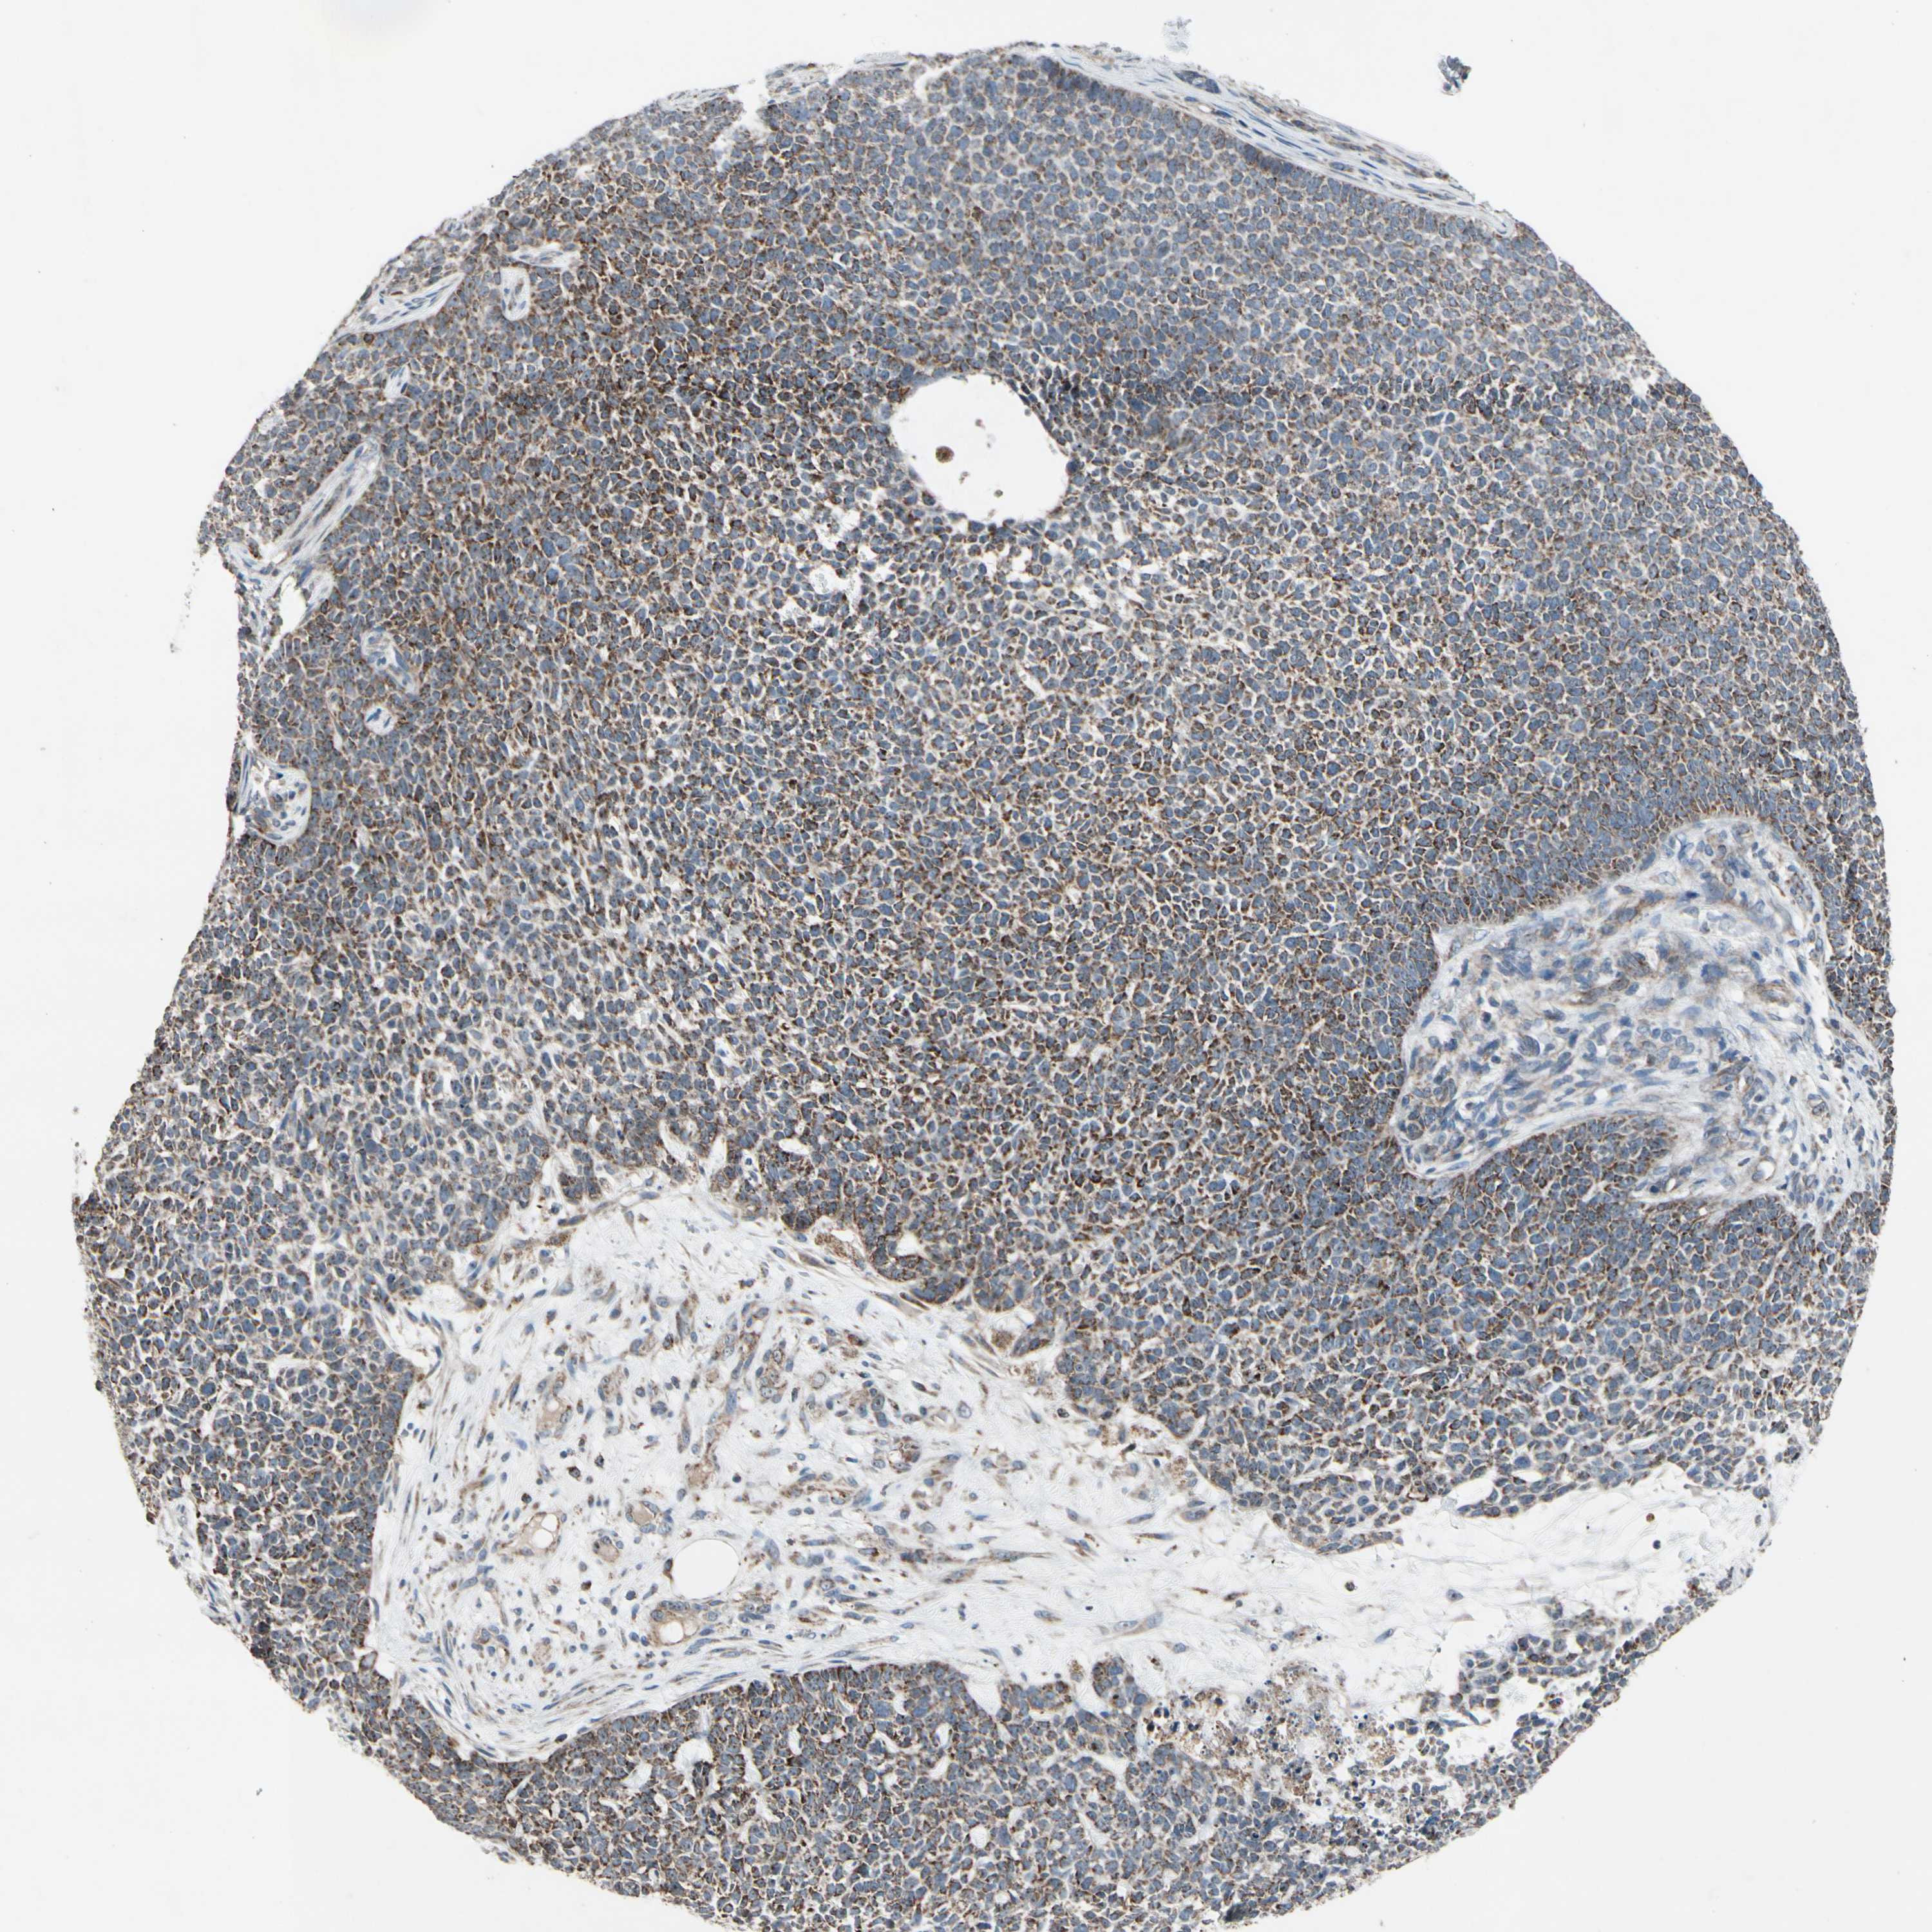

SKIN CANCER - Protein expressioni

A mouse-over function shows sample information and annotation data. Click on an image to view it in a full screen mode. Samples can be filtered based on level of antibody staining by selecting one or several of the following categories: high, medium, low and not detected. The assay and annotation is described here.

Each image is clickable and will lead to virtual microscopy that enables deeper exploration of all samples and also displays staining intensity scores, fraction scores and subcellular localization as well as patient and tissue information for each sample.

Antibody HPA008835

Staining

Medium

Intensity

Weak

Quantity

<25%

Location

Cytoplasmic/membranous

Squamous cell carcinoma, NOS

Basal cell carcinoma